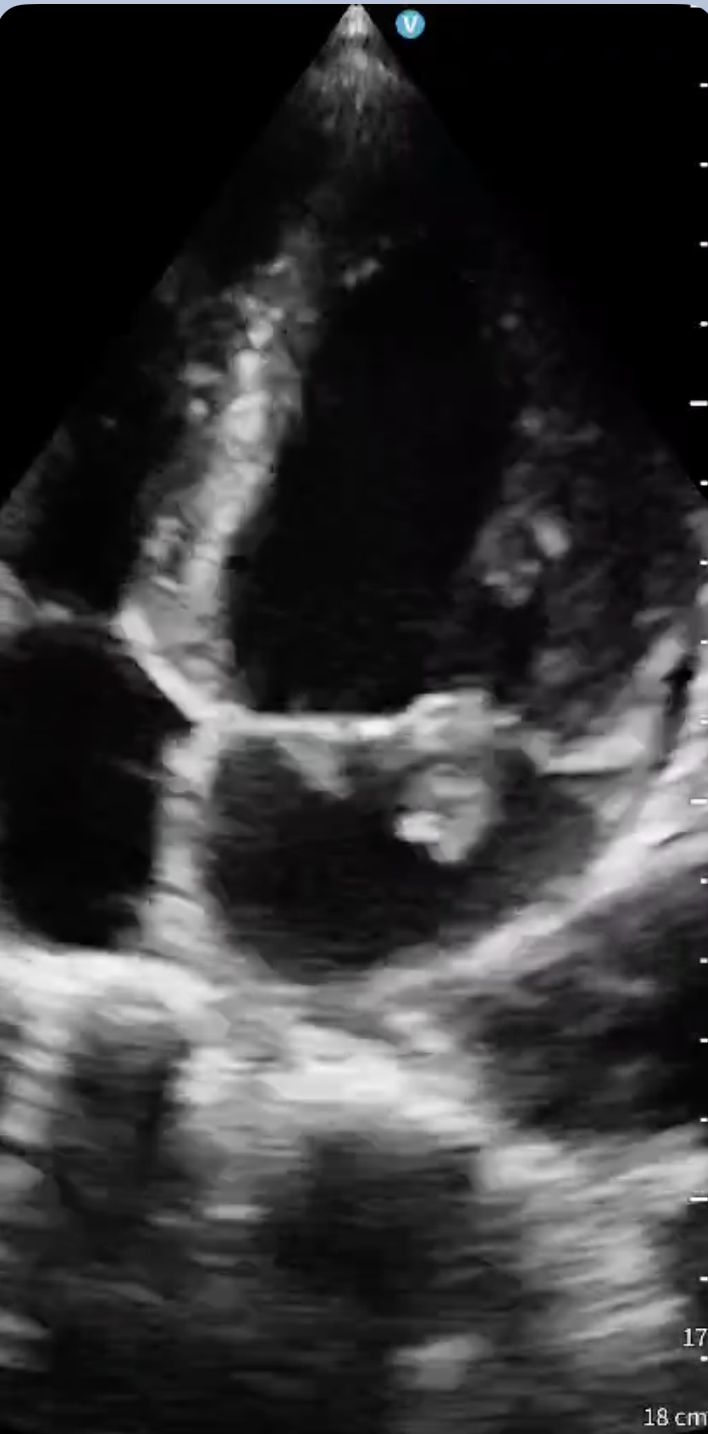

Hombre de 38 años, consumidor de múltiples sustancias, trasladado a Urgencias tras hallarse en vía pública con bajo nivel de conciencia, fiebre y taquicardia. Presenta Glasgow 9, orientación conservada pero obnubilación, y auscultación cardiopulmonar anodina. La analítica sanguínea evidencia leucocitosis con neutrofilia, elevación de proteína C reactiva, procalcitonina y troponina I ultrasensible. Las serologías son positivas para virus de la inmunodeficiencia humana y hepatitis C, y el cribado toxicológico para cannabis y cocaína. Durante la estancia en Urgencias empeora neurológicamente, realizándose tomografía cerebral que muestra ictus isquémico en territorio de la arteria cerebral posterior derecha. Dados los antecedentes, la primera sospecha es la de origen cardioembólico, así que se realiza ecocardiografía clínica a pie de cama, objetivándose válvula mitral con velos engrosados y gran vegetación de 5×8 milímetros que prolapsa hacia aurícula generando insuficiencia mitral severa. Se observa además válvula aórtica trivalva engrosada con vegetaciones en todos los velos, compatible con endocarditis infecciosa.

En un paciente febril, consumidor de tóxicos y con deterioro del nivel de conciencia, se plantea diagnóstico diferencial entre sepsis de origen no filiado, infección del sistema nervioso central, intoxicación aguda e infarto cerebral. Tras el resultado de la tomografía, la cardiopatía estructural embólica pasa a ser la primera causa a descartar. El hallazgo ecográfico resulta determinante para identificar el origen cardioembólico y orientar el cuadro como endocarditis infecciosa complicada con embolización cerebral.